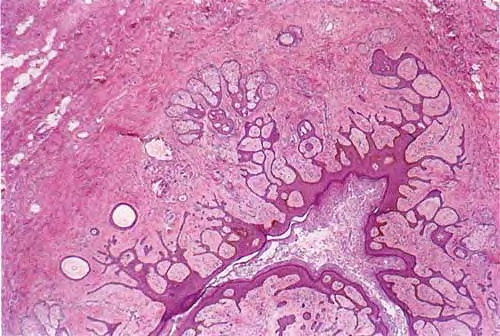

Trichofoliculoma =ورم جريبي شعري